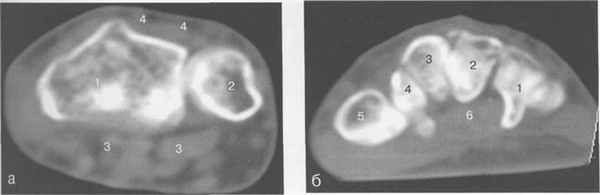

Рис. 19.56. КТ лучезапястного сустава.

а —через плоскость лучезапястного сустава: 1 —лучевая кость; 2 — локтевая кость; 3 — сухожилия мышц-сгибателей; 4 — сухожилия мышц-разгибателей.

б — через плоскость костей запястья: 1 — крючко-видная кость; 2 — головчатая кость; 3 — трапецие-видная кость; 4 — кость-трапеция; 5 — основание I пястной кости; 6 — сухожилие мышц сгибателей, в — через плоскость пястных костей: 1 — Т пястная кость; 2 — II пястная кость; 3 — III пястная кость; 4 — IV пястная кость; 5 — V пястная кость; 6 — сухожилие m. flexor pollicis longus; 7 — ладонный апоневроз; 8 — сухожилия мышц-сгибателей.

наличии патологических изменений. Только в этой плоскости можно адекватно оценить ана-томо-топографические соотношения лучелоктевого сустава и диагностировать минимальные ладонные и тыльные подвывихи (рис. 19.56).